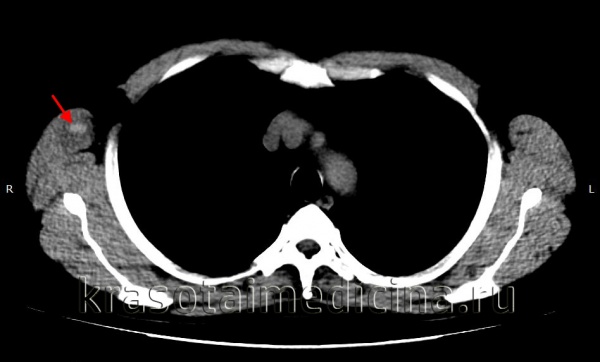

image

КТ головного мозга. Гематома периферических мягких тканей левой теменной области